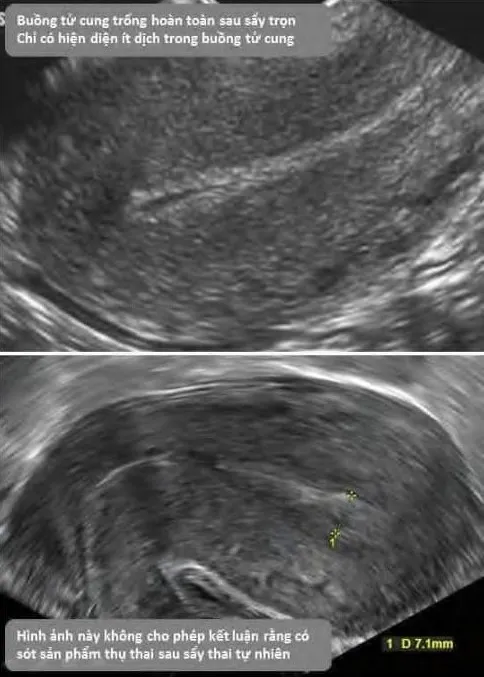

Sảy thai trọn

Phần tiêu đề “Sảy thai trọn”Hoàn toàn tống xuất mô thai, cổ tử cung đóng, siêu âm buồng tử cung rỗng hoặc chỉ có ít dịch.